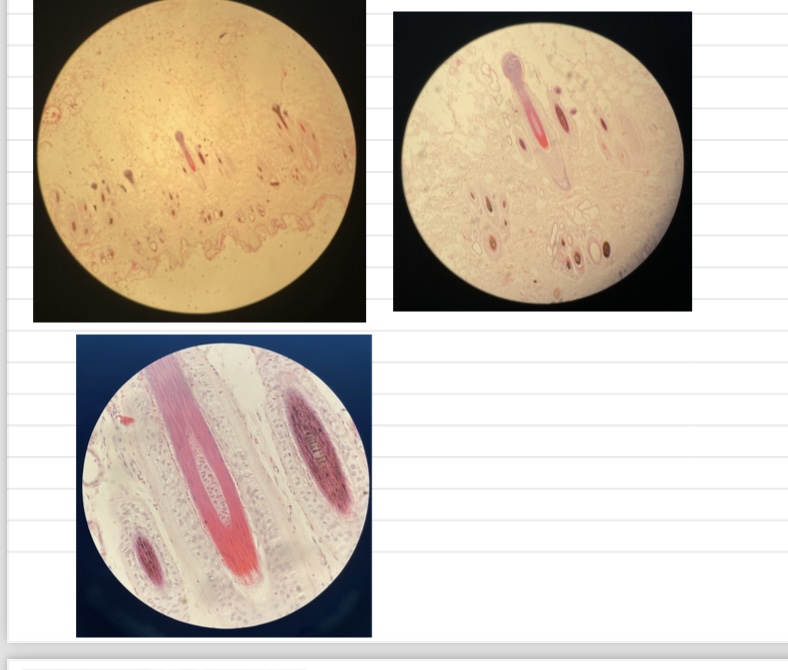

Trichinellosis

- Early: parasite within myocytes +infiltrate cells

- Late: normal morph w/ thick capsule and possible accumulation of Ca salt